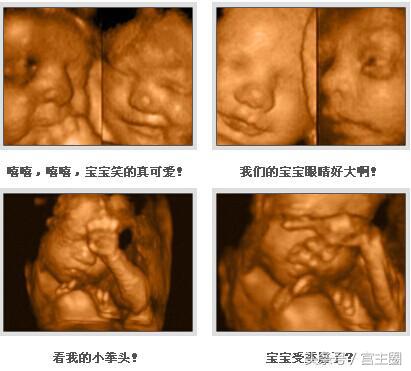

第三次检查:可于孕26周左右进行。此期胎儿皮下脂肪较以上饱满,面部表情也比较丰富,胎儿各个部位较前期更加清晰,不仅是对以上各类畸形的诊断更加明确,而且胎儿面部的各种表情,如吃手指、打呵欠、哭闹、喝羊水等表情清晰可见。